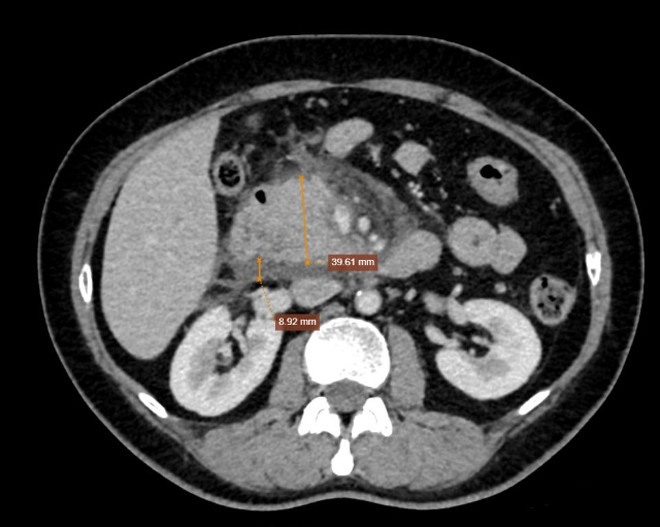

Chụp cắt lớp vi tính (CT-Scanner) ổ bụng có đầu tụy tăng kích thước, đường kính xấp xỉ 40mm. Bờ tụy đều, xung quanh tụ dịch dày 8mm, dịch lan ra khoang cạnh thận phải, gốc mạc treo dày 5mm. Hình ảnh viêm tuỵ cấp (Balthazar D).